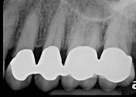

Fig. 2: Precision Fit Verification of Custom-Crafted Crown

Why is it that our crowns last for such a long time? Attention to detail with the tooth preparation and temporization, taking the clinical or digital impression, and the fabrication in our in-house laboratory are key to obtaining precision results. Our technician hand-crafts each crown and evaluates the precision of the fit. Finally, all crowns are X-rayed to ensure that the anticipated crown fit has been achieved. If not, we simply redo the crown. It must be perfect.

The precision doesn’t stop with the initial fitting. We use advanced imaging techniques to verify the margins and ensure there are no gaps where decay could develop. This meticulous approach is why our patients enjoy crowns that function beautifully and look natural for decades.